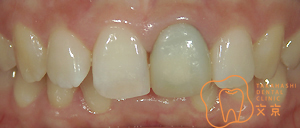

■前歯を治したい。 オールセラミックスによる審美治療

■前歯を治したい。40代男性 オールセラミックスによる審美治療

■前歯を治したい 精密審美治療・セラミックス治療

■前歯 精密審美治療

■前歯のセラミックス治療 審美治療

■前歯のオールセラミックス治療

■保険の前歯を直したい

■前歯が折れてしまった、、、